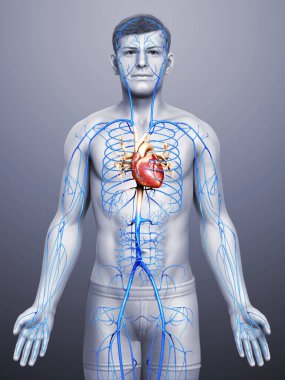

Kalbin anatomik incelemesi. Kalp sorunları, kalp krizi. Ameliyat mı? 3D görüntüleme. Siluet. Kalp, dolaşım sisteminin kan damarlarına kan pompalayan kaslı bir organdır.

Kırmızıİzole edilmişİnsanSağlıkBaşıİlaçSağlık hizmetlerierkekTıbbidikkatAdamsiyahYapıKardiyolojikalpHastagövdeKarnıEğitimİçeridebiyolojiBilimSistemGöğüsSaldırın!AcıorgvenKasÇizelgeİskeletanatomiKas gücübeyindiyagramBilim kurgux ışınısindirimAğrıKardiyakiskeletanatomikkoronerkalp krizi3d oluşturmakaslı organBenzer İçerikler